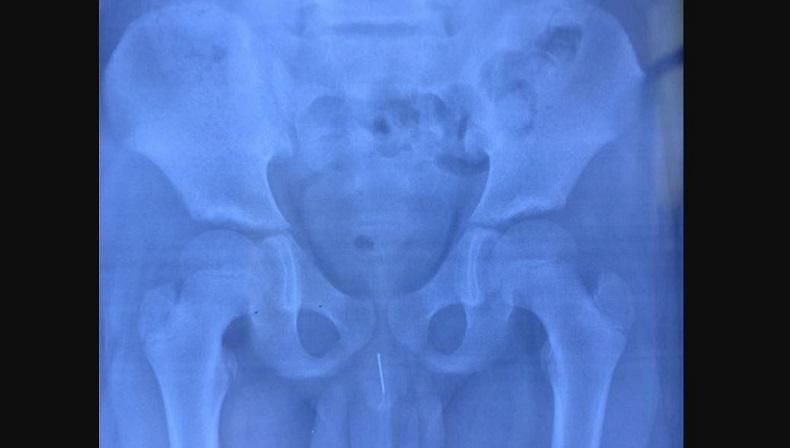

Dokter di China terkejut bukan main mendapati jarum akupuntur 8 cm ada di uretra penis bocah 11 tahun. (Foto: Jiangxi Children's Hospital/AsiaWire)